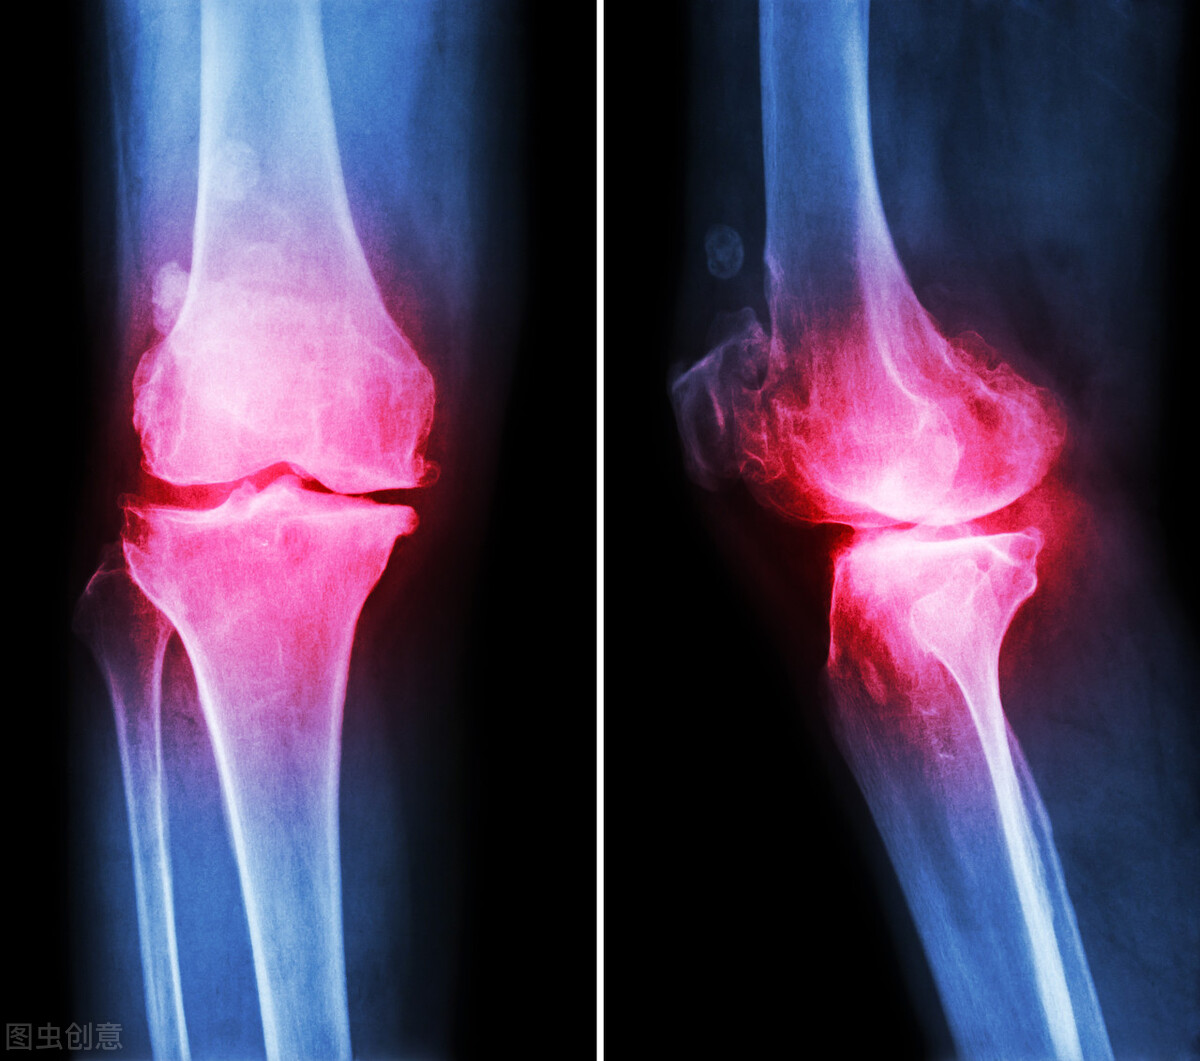

骨刺是什么?

骨刺,其实是人衰老后自然生长的产物。人衰老时,关节会随着退化,比如出现关节软骨磨损、变形,这个时候人体为了让关节稳定,那么就会在关节软骨附近产生一些骨赘,使整个关节紧绷起来,恢复稳定性。那么这个骨赘,就是被称为骨刺。这是一种代偿现象,就跟人老了长皱纹,长白发一样的情况。

上面我们已经知道,关节磨损的时候就会长出骨刺。那么当你的关节负荷越大,使用频率越高,你的关节就磨损越厉害,自然长出的骨刺就越大越多,这是为了给关节支撑,但是人体它没想到神经跟肌肉,所以当骨刺越长越大的时候会压迫到神经时会产生痛觉,而有些人会出现骨刺的微骨折引起发炎,导致关节肿大,也会出现疼痛。